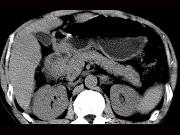

问题 女,63岁,右上腹疼痛,呈不规律性钝痛,伴恶心,时有呕吐,呕吐物为胃内容物混有胆汁,CT检查如图,最可能的诊断是()

选项 A.十二指肠克罗恩病 B.十二指肠结核 C.十二指肠癌 D.十二指肠淋巴瘤 E.十二指肠平滑肌瘤

答案 C